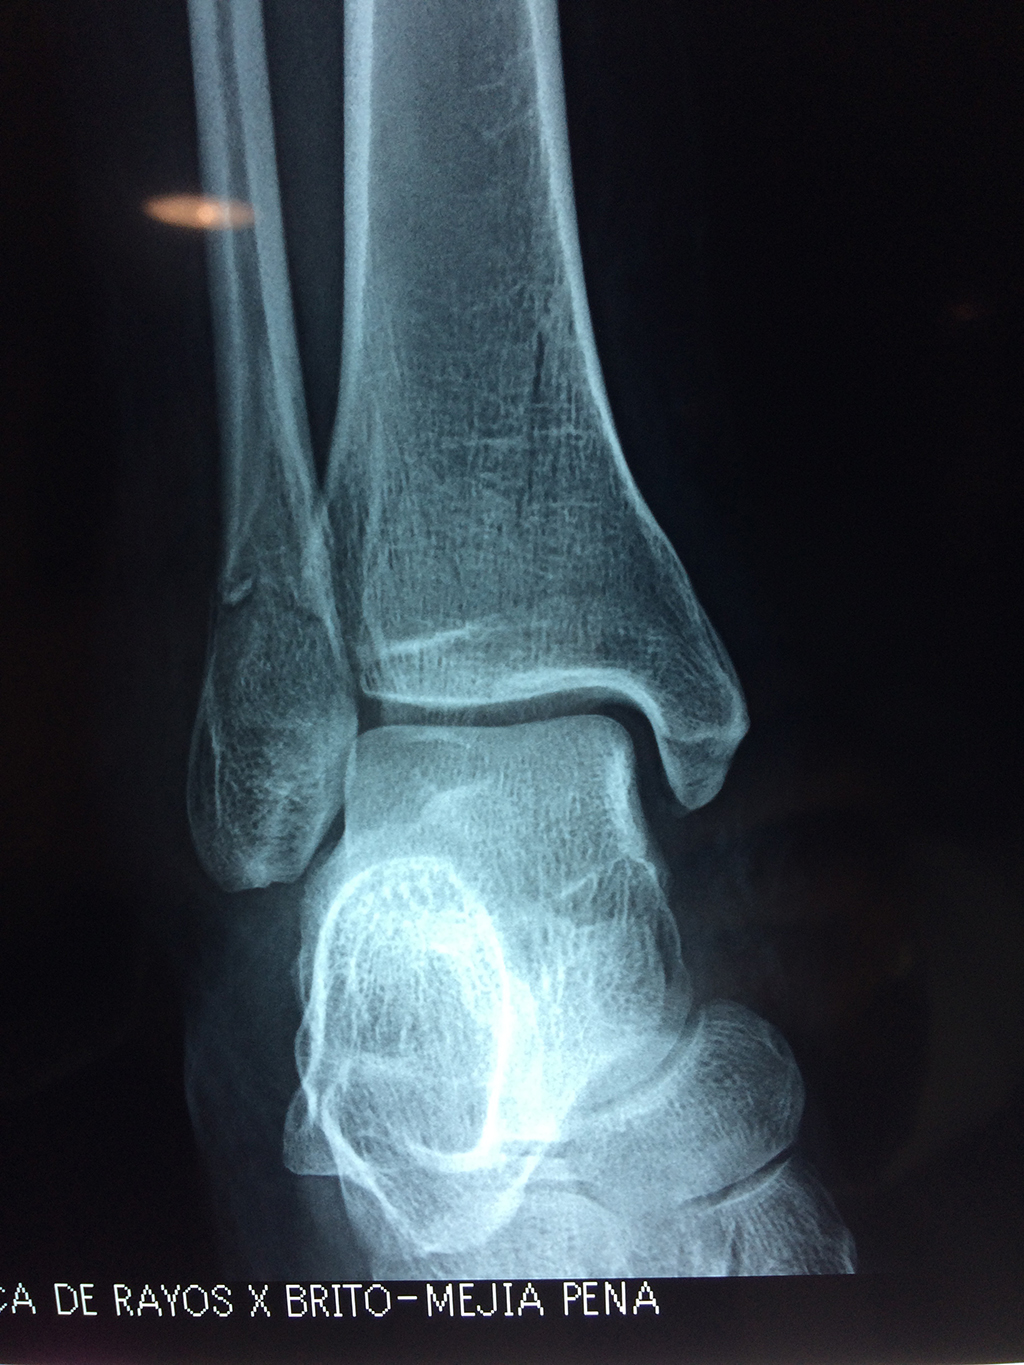

Una fractura de tobillo es la rotura de uno o más de los huesos del tobillo. Estas fracturas pueden ser:

Algunas fracturas de tobillo pueden requerir cirugía si:

- Los extremos de los huesos están desalineados entre sí (desplazados).

- La fractura se extiende hasta la articulación del tobillo (fractura intra-articular).

- Los tendones o ligamentos (tejidos que sujetan los músculos y los huesos entre sí) están rotos.

- El médico cree que sus huesos probablemente no sanen apropiadamente sin cirugía.

- El médico considera que la cirugía puede permitirle una recuperación más rápida y confiable.

- En los niños, la fractura involucra la parte del hueso del tobillo donde el hueso está creciendo.

Cuando se necesita cirugía, es probable que esta implique el uso de clavijas de metal, tornillos o placas para sostener los huesos en su lugar mientras la fractura se consolida. Los elementos de soporte pueden ser temporales o permanentes.